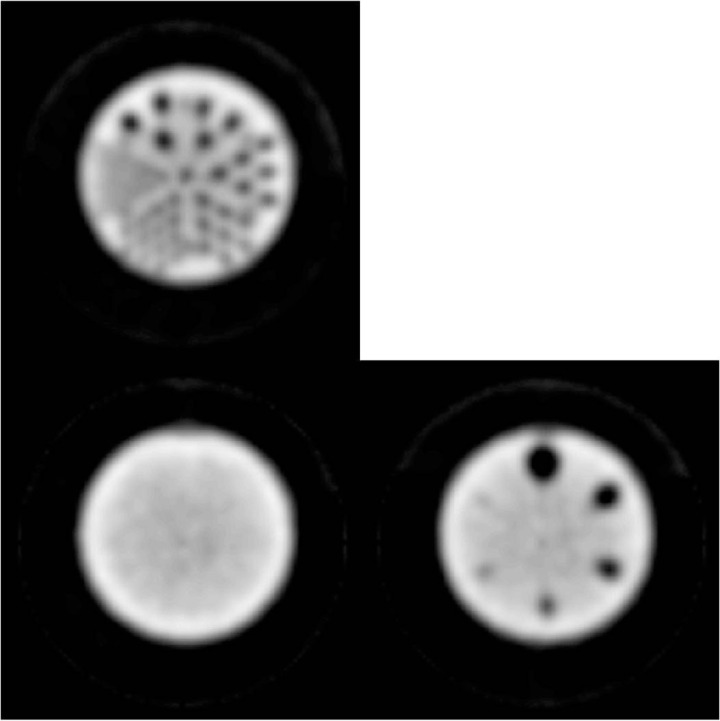

Figure 4.

ACR phantom images without attenuation correction: Rod image (top) from summation of five sections demonstrating high SPECT resolution; uniformity image (bottom left) demonstrating bright ring due to lack of attenuation correction and coarse noise likely due to reconstruction algorithm; sphere image (bottom right) demonstrating excellent cold contrast even without attenuation correction.